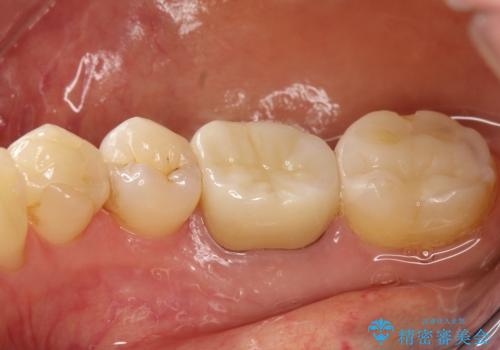

咬んだ時の違和感 顕微鏡で発見された歯の穴を処置し、かみ合わせを回復する

- 再根管治療にて発見されたパーフォレーションを修復し、改めてかぶせ物を製作する。

かぶせ物の種類:Bellezza